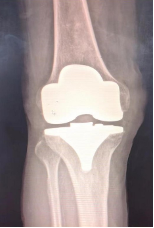

全膝置换术:是治疗膝关节骨性关节炎的金标准,可以有效消除或缓解疼痛症状,改善患者运动功能,矫正患肢力线,提高患者生活质量。但是全膝置换术切除了前后交叉韧带、半月板,手术创伤大,术中出血量大,术后恢复慢,膝关节功能不完善,并且全膝置换术属于终极手术,截骨量多,术后翻修困难。

(全膝置换术后影像)